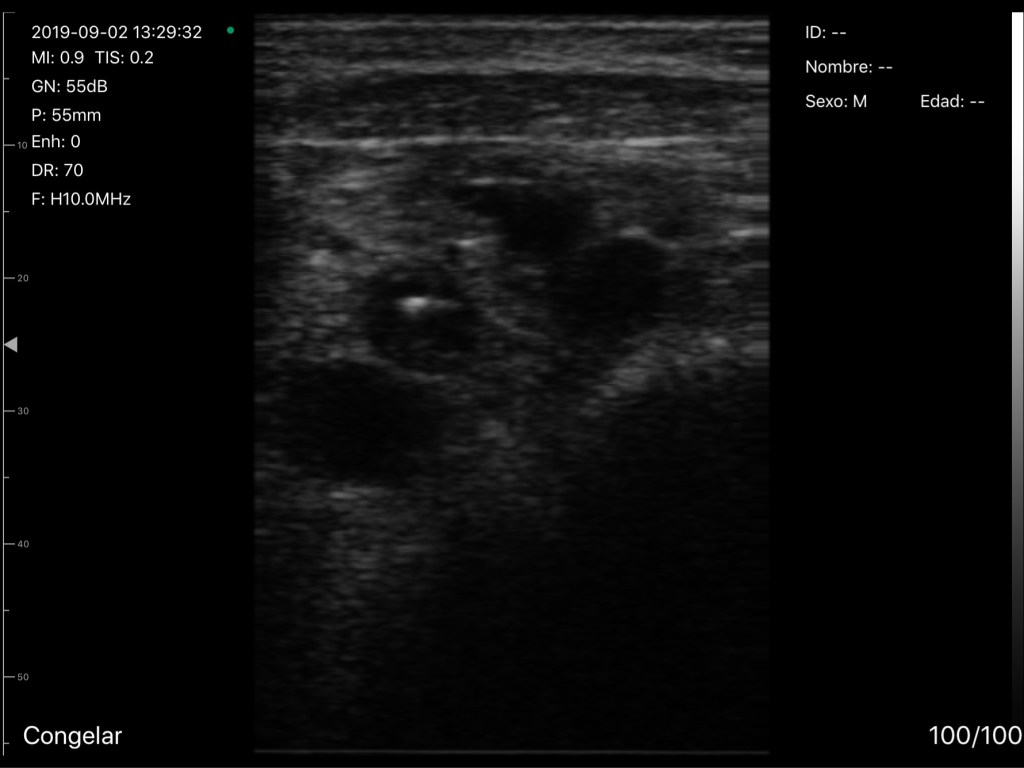

Antecedentes: El acceso intravenoso difícil (DIVA) es un problema común en los servicios de urgencias (SU), sin embargo, la prevalencia y el impacto clínico de esta condición es poco conocida. La inserción de un catéter intravenoso periférico guiado por ultrasonido (USGCVP) es una modalidad exitosa para obtener acceso intravenoso (IV) en pacientes con DIVA.

Métodos: Consultamos retrospectivamente la historia clínica electrónica de todos los pacientes de urgencias que tenían una vía intravenosa periférica (CVP) insertada en un centro médico académico terciario de 2015 a 2017. Clasificamos a los pacientes como con DIVA si requerían ≥3 punciones de CVP o una USGCVP. Comparamos las métricas para la prestación de atención, incluido el tiempo transcurrido hasta el acceso intravenoso, el tiempo transcurrido hasta los resultados de laboratorio, el tiempo transcurrido hasta la analgesia intravenosa y la duración de la estancia en el SU entre pacientes con y sin DIVA.

También comparamos estas métricas en pacientes con DIVA con un USGCVP insertado por un médico versus aquellos con un USGCVP insertado por una enfermera.

Resultados: Se evaluó a un total de 147,260 pacientes durante el período de estudio. De estos, 13.192 (8,9%) cumplieron los criterios para DIVA. Los pacientes con DIVA encontraron retrasos estadísticamente significativos en el tiempo hasta el acceso intravenoso, el tiempo hasta los resultados de laboratorio, el tiempo hasta la analgesia intravenosa y la estancia en SU en comparación con los pacientes sin DIVA (todos p <0,001).

Los pacientes con USGCVP insertados por enfermeras también tuvieron mejoras estadísticamente significativas en el tiempo hasta el acceso intravenoso, el tiempo hasta los resultados de laboratorio, el tiempo hasta la analgesia intravenosa y la estancia en SU en comparación con los pacientes con USGCVP insertados por el médico (todos p <0,001).

Conclusión: DIVA afecta a muchos pacientes en servicios de urgencias y conduce a retrasos en la atención relacionada con la obtención de un CVP. La inserción del CVP con ultrasonido por enfermeras mejora la atención en pacientes con DIVA.